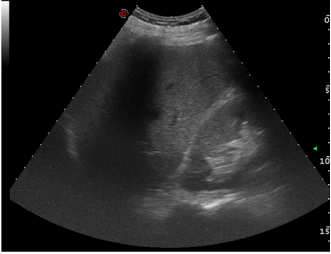

The case from the article: “A man presented to the emergency department with a stab wound to his right upper quadrant. His vital signs were in the normal range. Examination revealed a 1.5 cm wound at the junction of the subcostal margin and the linea semilunaris. There was localised peritonitic tenderness. Lactate was elevated at 4.3 mmol/l. FAST ultrasound (focused assessment with sonography for trauma) was performed. Initial perihepatic imaging did not reveal fluid in Morison’s pouch.

In the course of this imaging, a thin anechoic strip was noticed around the gallbladder